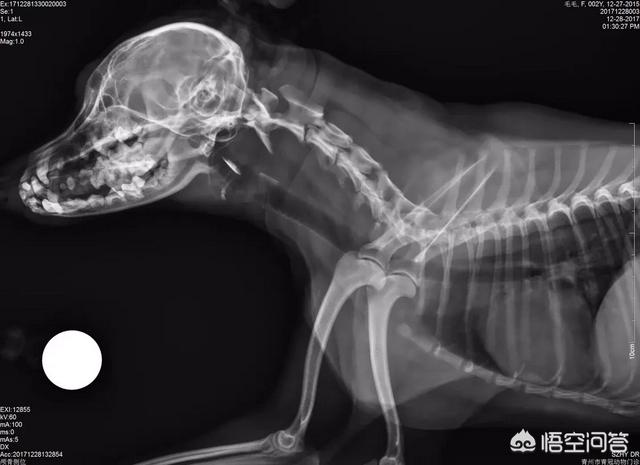

如果患腰椎疾病,由于疼痛引起不敢排便;或支配神经和排便中枢受损后不能支配,引起便秘。这个需要做神经学的检查。

狗狗食物中的纤维素的含量过低,同样可引起便秘,同时吃肉过多,就会造成便秘,还有最近有没有吃骨头。排便疼痛性疾病,如肛门狭窄、肛门脓肿等。腰荐部脊髓损伤、骨盆骨折、肠疝、肠肿瘤及肠道寄生虫等。内分泌紊乱导致的甲状腺功能亢进和减退而引起的结肠平滑肌减退。全身衰竭和高度脱水可引发该病。还有就是年龄问题。

若想快速消除便秘症状,则用清洁温水、肥皂水或石腊油、开塞露等灌肠。最好37度,粪便如过于硬实,建议去医院找医生,可用手指在腹后部隔着皮肤捏压直肠结粪,使其变小,容易排出,有时还需要使用卵圆钳或手术镊夹出粪块。

尽量早点治疗,如以上方法均难以排除因便秘日久而在直肠、结肠内形成的坚硬粪块,就需施行肠管切开术取出粪块。